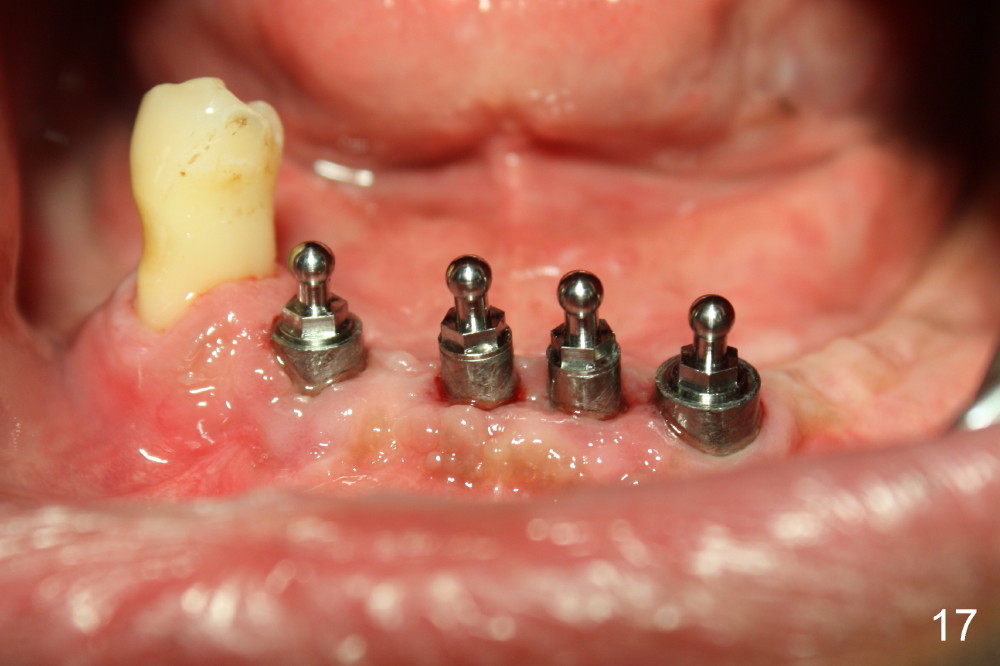

The 4 anterior implants appear to have been osteointegrated 5 months postop (Fig.14,15). More gingiva has covered the top portion of the implants (Fig.16). Ball abutments are placed for an overdenture (Fig.17).